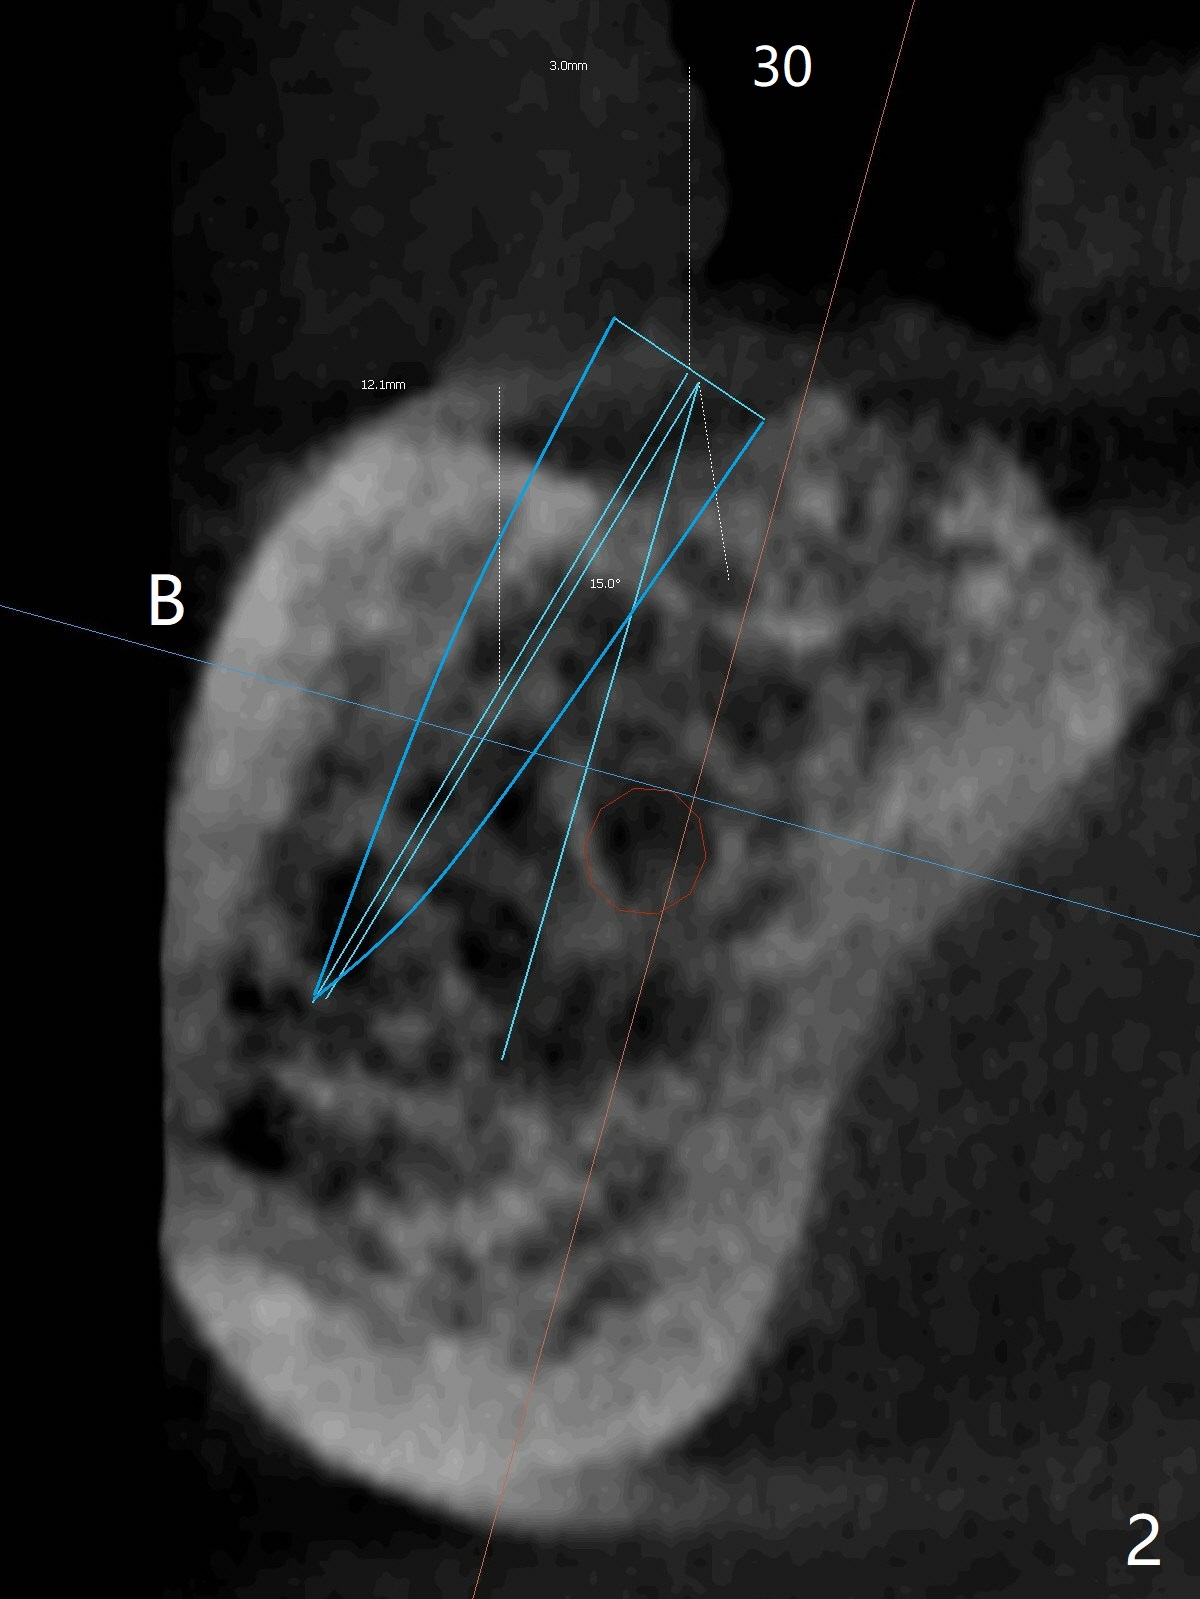

Following placement of a 3 mm 1-piece implant at #26 and two 3.8 mm 2-piece implants with ball abutments at #20 and 21 for a lower edentulous patient, another implant with ball abutment will be placed posterior (approximately at #30, Fig.1,2 (for better spread)) or anterior (approximately at #28, Fig.3,4). The implant will be placed buccal (Fig.2) or lingual (Fig.4) to the Inferior Alveolar Canal or Incisive Canal (safer). Or an implant can be placed at #27, in which there have been 2 implant failures. The last implant was removed 3 months 20 days earlier. Make an incision, study whether the site of #27 has healed with solid bone. If an implant has to be placed at #28, dissect the Mental Nerve first. When stability is low, bury the implant.